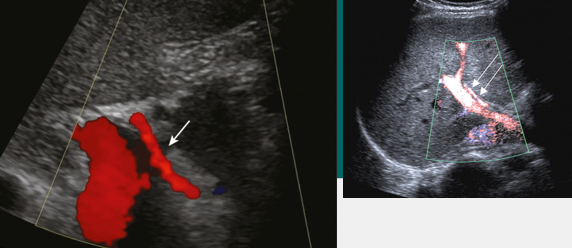

HA to PV fistula (AVF)